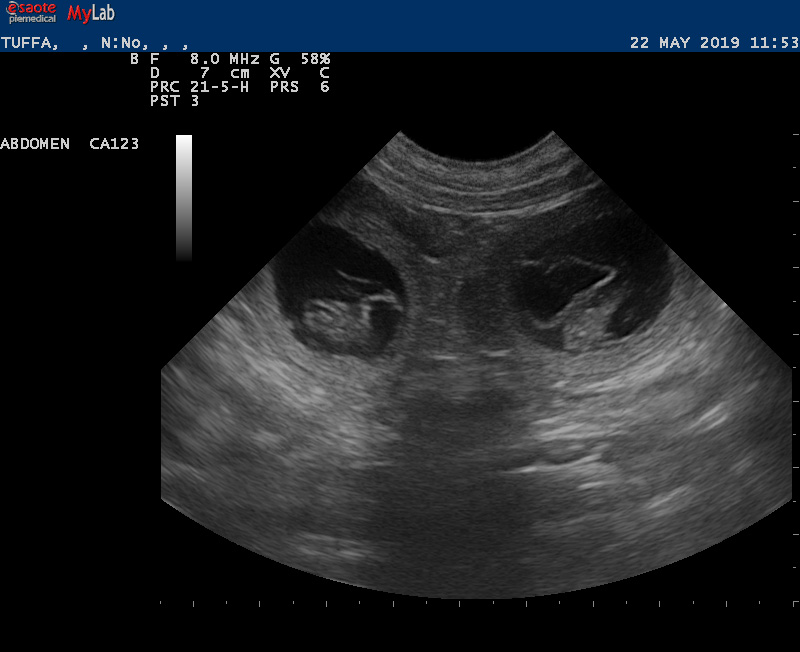

Lotta är dräktig!!

Vi har gjort ultraljud och det finns många valpar i Lottas mage!! Stolt pappa är Bertil (Actualis Winter Surprise).

Valparna föds i mitten av januari och vill flytta till sina nya familjer i matten av mars.